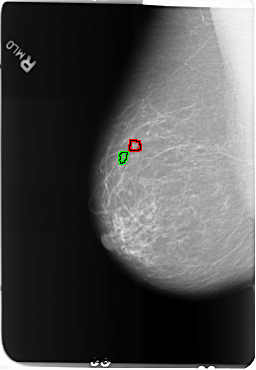

B_3502_1.RIGHT_MLO

FILE: B_3502_1.RIGHT_MLO.OVERLAY

TOTAL_ABNORMALITIES 2

ABNORMALITY 1

LESION_TYPE CALCIFICATION TYPE PLEOMORPHIC DISTRIBUTION CLUSTERED

ASSESSMENT 4

SUBTLETY 3

PATHOLOGY MALIGNANT

ABNORMALITY 2